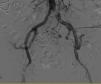

A pesar de que la ecografía Doppler, repetida en 2 ocasiones, no sugiere estenosis de arteria renal, se decide arteriografía en la que se objetiva obliteración de la porción distal de la ilíaca común izquierda (fig. 1), permeabilidad del resto del eje ilíaco y de la arteria del injerto renal. Se predilata y se coloca un stent a nivel de la obliteración, con recuperación casi completa del calibre vascular (fig. 2).